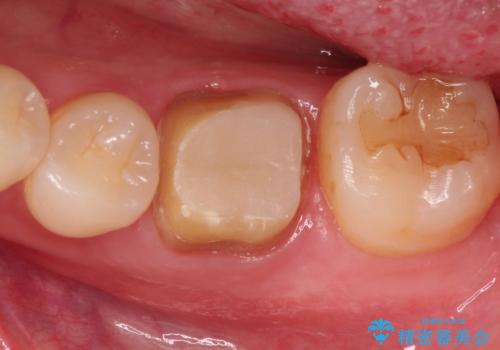

- 下の奥歯の銀歯を白くしたいとのことで来院されました。

痛みなどの症状はなく、前に根管治療を行っている歯になります。

古い銀歯を除去し、審美性の良いセラミッククラウンでの治療を行うこととしました。

銀歯を除去し、セラミッククラウンに替えました。

審美性が良くなるだけでなく、拡大鏡を使用した治療、精度の高い材料の使用によって、虫歯の再発リスクを減らすことができます。